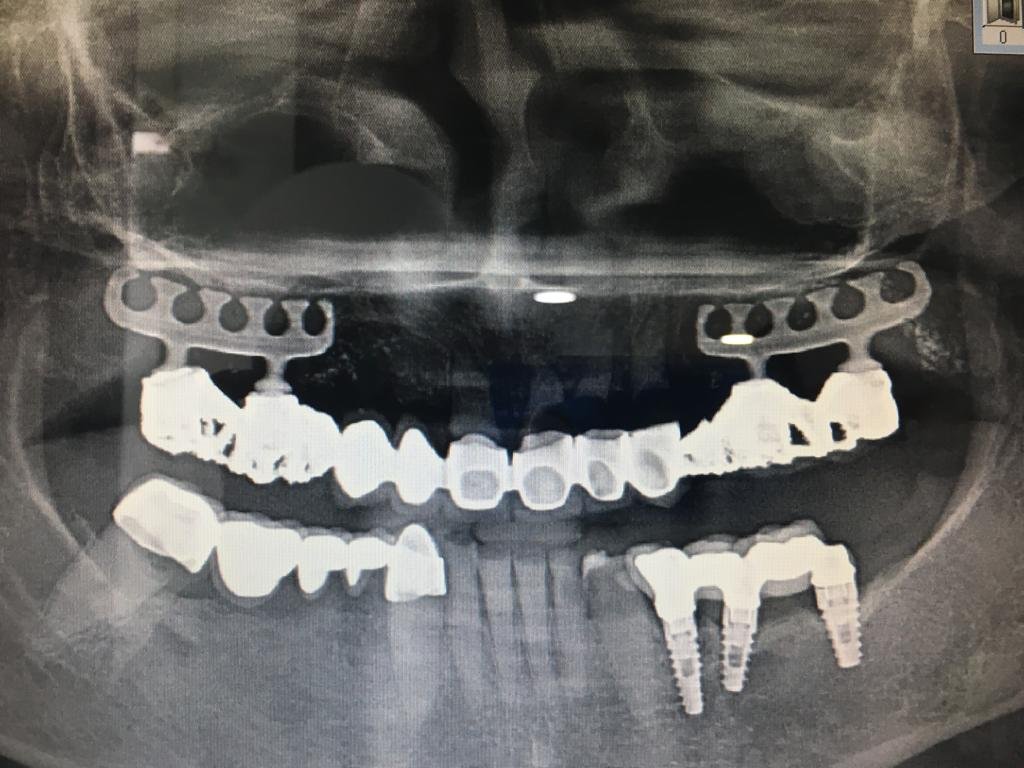

Buenas tardes compañeros, necesito saber el tipo de implante que tiene esta paciente en las posiciones 36 y 37. No sé ni puedo ver las conexiones pues sigue cementada la [...]

Paciente de 60 años, se colocó implantes hace 20 años, acude a nuestra consulta para cambiar prótesis híbrida. Necesito saber que implantes lleva creemos que son de conexión interna. Además [...]